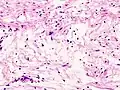

Micrograph of a schwannoma showing both a cellular Antoni A area (top) and a loose paucicellular Antoni B area (bottom). HE stain.